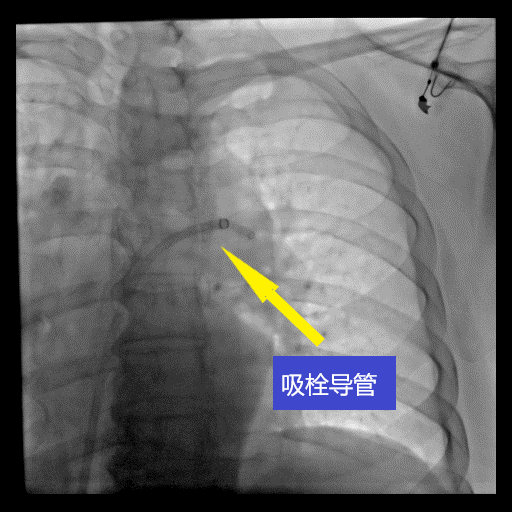

尽管李大妈的病情缓解了,但是叶钢主任在检查中发现李大妈的右心室已经增大,并且心肌酶明显增高,根据急性肺动脉栓塞的危险分层,属中高危阶段,李大妈的病情仍然比较危重,遗留远期肺动脉高压的可能性很大,遂向血管外科发出了会诊申请。经过综合评估,并与患者家属进行充分沟通后,血管外科赵亮主任决定为李大妈进行肺动脉造影及肺动脉血栓抽吸溶栓手术。这是目前一项比较先进的手术技术,通过微创介入,在患者的大腿根部静脉穿刺一个小孔,将一根细导管送到肺动脉内,连接负压吸引装置,将堵塞肺动脉的大块血栓抽吸出来,而通过导管注射小剂量的溶栓药,将会把残余的小血栓溶化,从而恢复肺动脉的血流供应,满足正常的气体交换。

在赵亮主任的指导下,赵辉主任医师与顾纵横主治医师全神贯注,动作流畅,操作精准,成功将肺动脉内的血栓清除,并在下腔静脉内安放了腔静脉滤器,以防下肢的深静脉血栓再次脱落栓塞肺动脉,整个手术用时一个小时。术后,李大妈立刻就感觉呼吸畅快了,不再憋气了。第二天,李大妈由急诊ICU转回血管外科病房,在医生的指导下可以正常下床行走活动,没有再发生喘憋的情况。